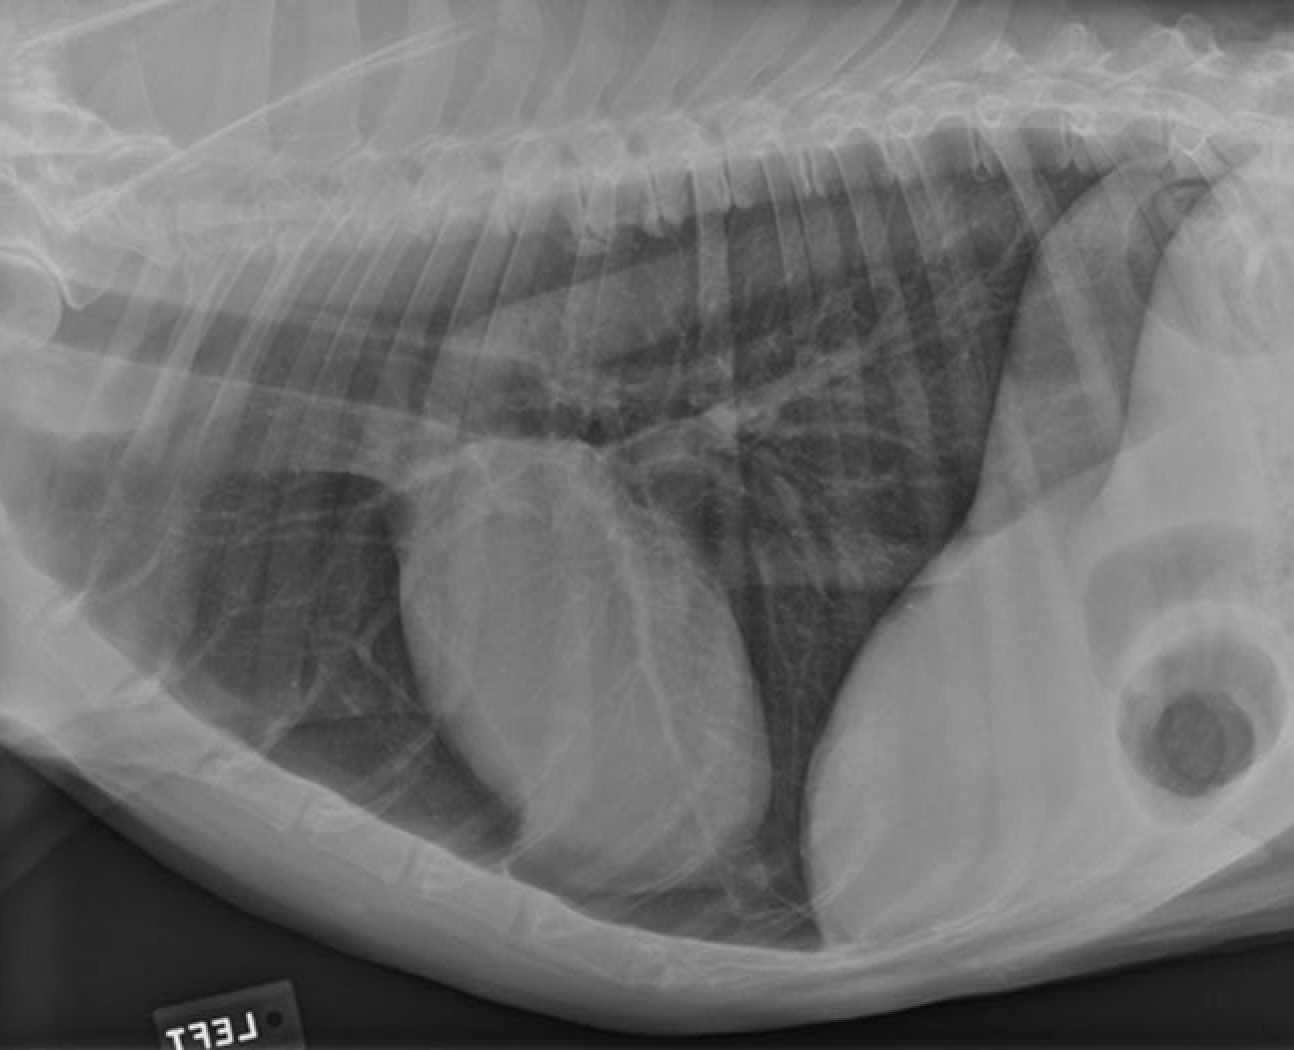

identify the structures

identify the pulomary arteries

identify the aorta

identify the ventral mediastiunum

identify the scapula

identify the ventral lung lobes